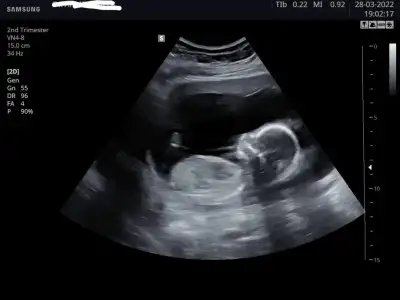

Bu kadar yakalayabildi, tekmelerden fırsat bulunca🤣, 7 Nisan'da enfeksiyon sonrası kontrole gidicem, belki o zaman poz verir koca göbüşlü 🤗

Bu kadar yakalayabildi, tekmelerden fırsat bulunca🤣, 7 Nisan'da enfeksiyon sonrası kontrole gidicem, belki o zaman poz verir🤗